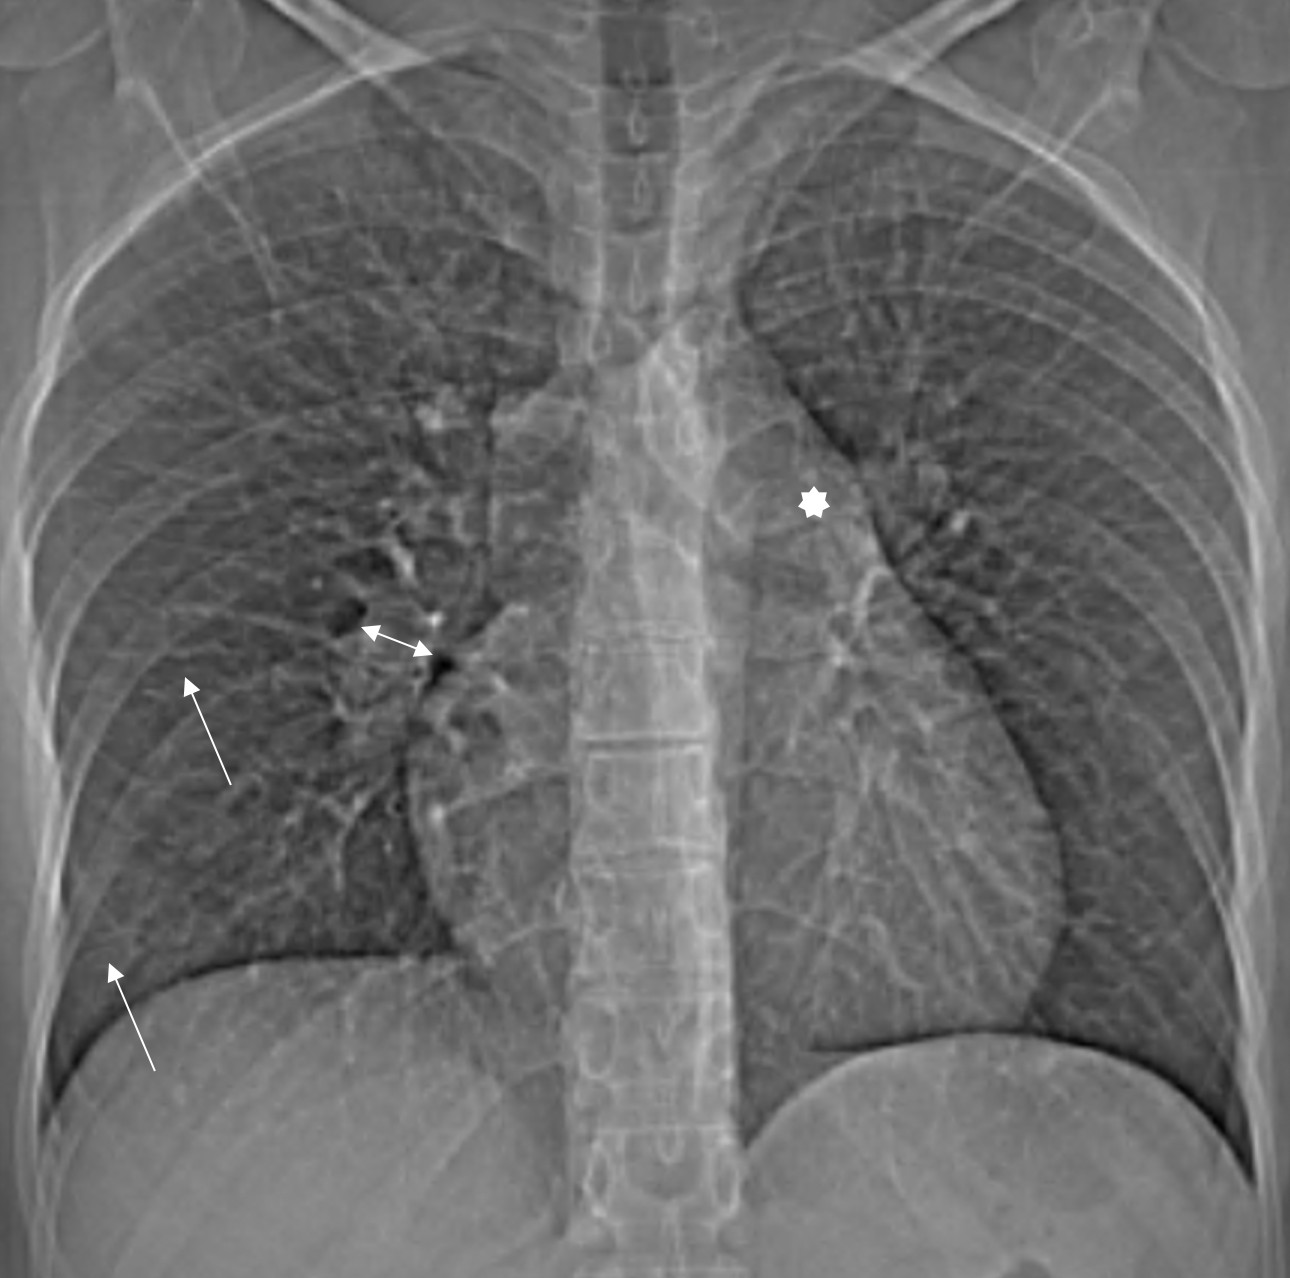

1. Рис.1 Рентгенограмма лёгких, прямая проекция. | |

5. Рис.5 Рентгенограмма лёгких, прямая проекция. | |